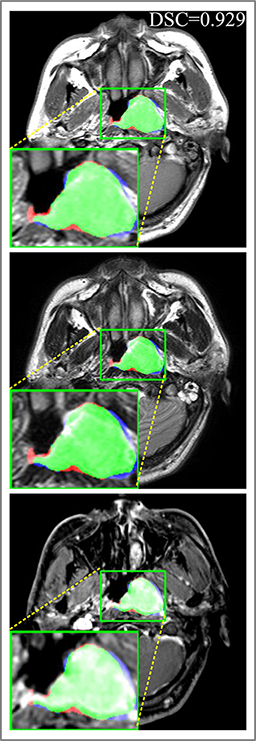

Comparison with ground truth. Some predicted results of MMFNet are shown in 2D images and 3D images in Figure 7 and Figure 8. As shown in these figures, although the shape and size of NPC are varied from each other, MMFNet can still accurately determine the regions of NPC and obtain the accurate contours of tumors. Through analyzing 2D images in figure 7, MMFNet has a capacity to fuse multi-modality MRI to reduce the confusion brought by intensity’ similarity between nearby tissues and NPC. The values of , and of MMFNet are shown in Table 1. MMFNet can reach the best results with , and .

Comparison with related works. Table 1 reports the values of , and for different methods. Predicted masks of different methods are illustrated in Figure 9 and Figure 10, which respectively present results in 2D and 3D images. Through comprehensively analyzing these results, the proposed MMFNet actually have the following properties: